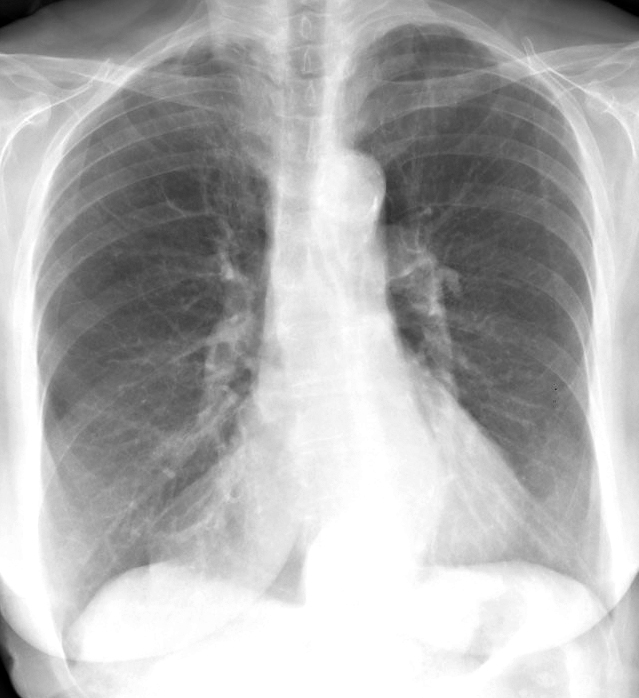

Fat Pad

Case 5a